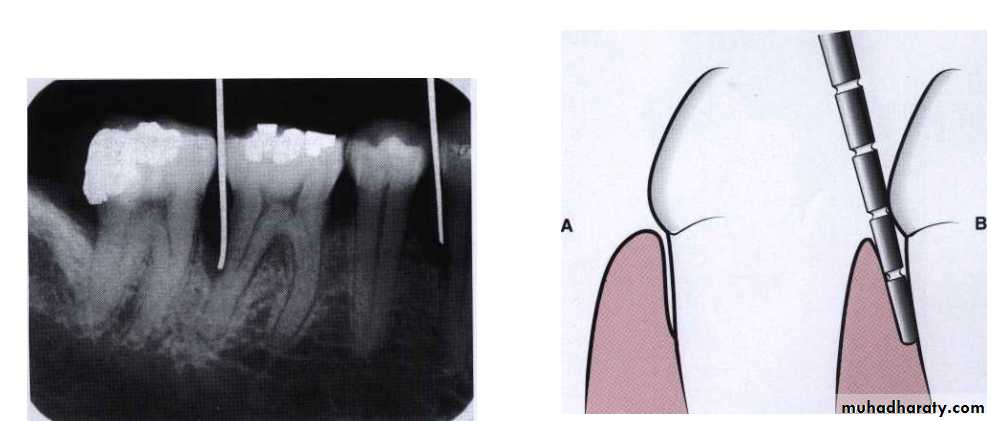

Detection of pocket: the only accurate method of detecting and measuring periodontal pockets is careful exploration with a periodontal probe.

Probing technique: The probe should be inserted parallel to the vertical axis of the tooth and walked circumferentially around each surface of each tooth to detect the areas of deepest penetration.

Pocket depth is the distance between the base of the pocket and gingival margin while the level of attachment is the distance between the base of the pocket and fixed point on the crown (cementoenamel junction), change in the level of attachment can be due only to gain or loss of attachment.Palpation: palpation the oral mucosa in the lateral and apical areas of the tooth may help locate the origin of radiating pain that the patient cannot localize.